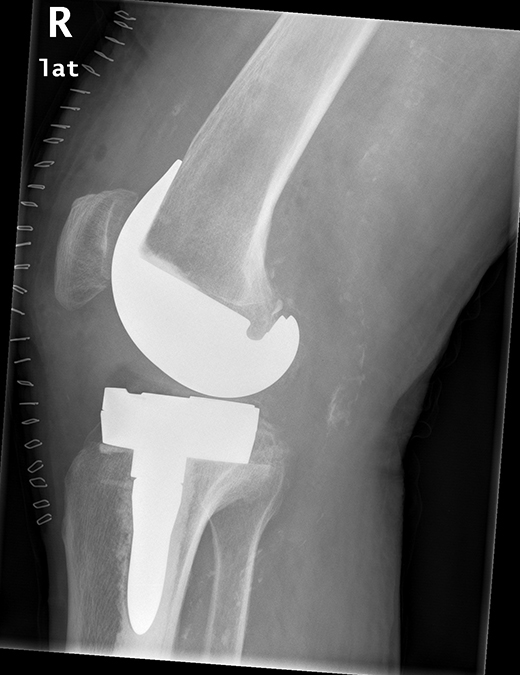

Versorgung mit Roboter assistierter Knieprothese mit Ausgleich des knöchernen Defektes durch Titan-Stufe auf der Innenseite.

Digitale Prothesenplanung

Postoperatives Resultat nach Versorgung mit Roboter assistierter Knieprothese mit Ausgleich des knöchernen Defektes durch Titan-Stufe auf der Innenseite.